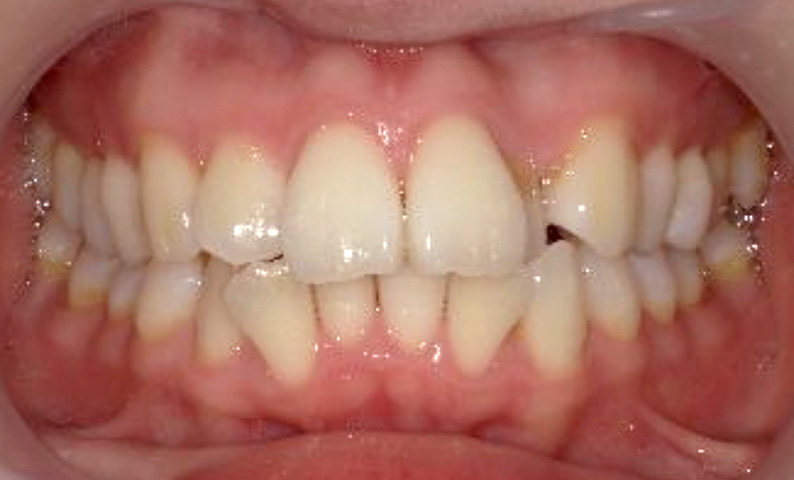

症例_024 上顎だけの部分矯正

治療期間:7ヶ月金額:30万円+税女性前歯のガタガタ上の前歯だけ

| Before | After |